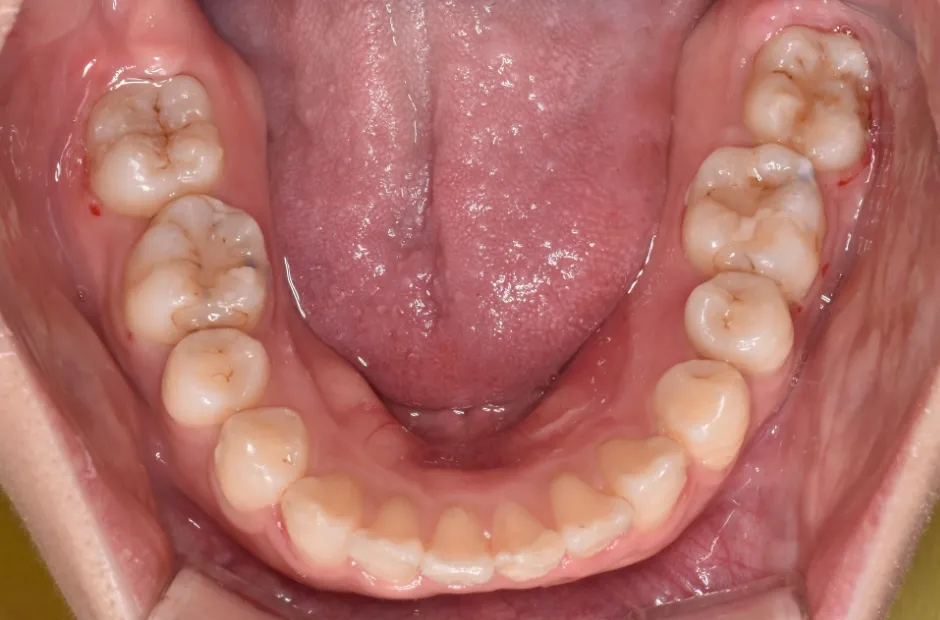

開咬

| 診断名・主訴 | 開咬 |

|---|---|

| 年齢・性別 | 18歳・男性 |

| 治療期間・回数 | 1年 12回 |

| 治療に用いた主な装置 | ロール付きリンガルアーチ |

| 抜歯部位 | なし |

| 治療費 | 70万円(税抜) |

| リスク・副作用 | 装置による違和感・疼痛・歯肉退縮・歯根吸収・虫歯のリスクなど |

治療後